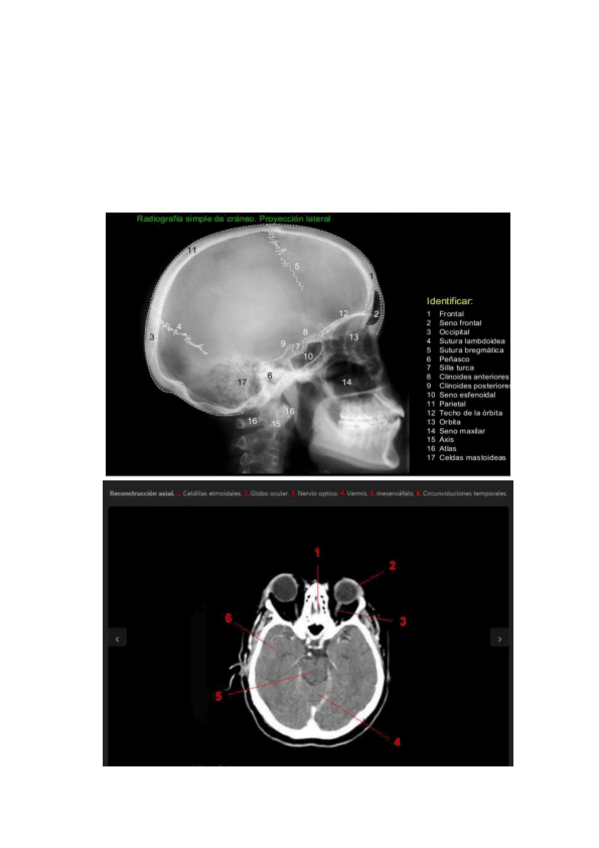

Apuntes - Tema-9-Cavidad-craneal.pdf

Apuntes - Tema-9.pdf